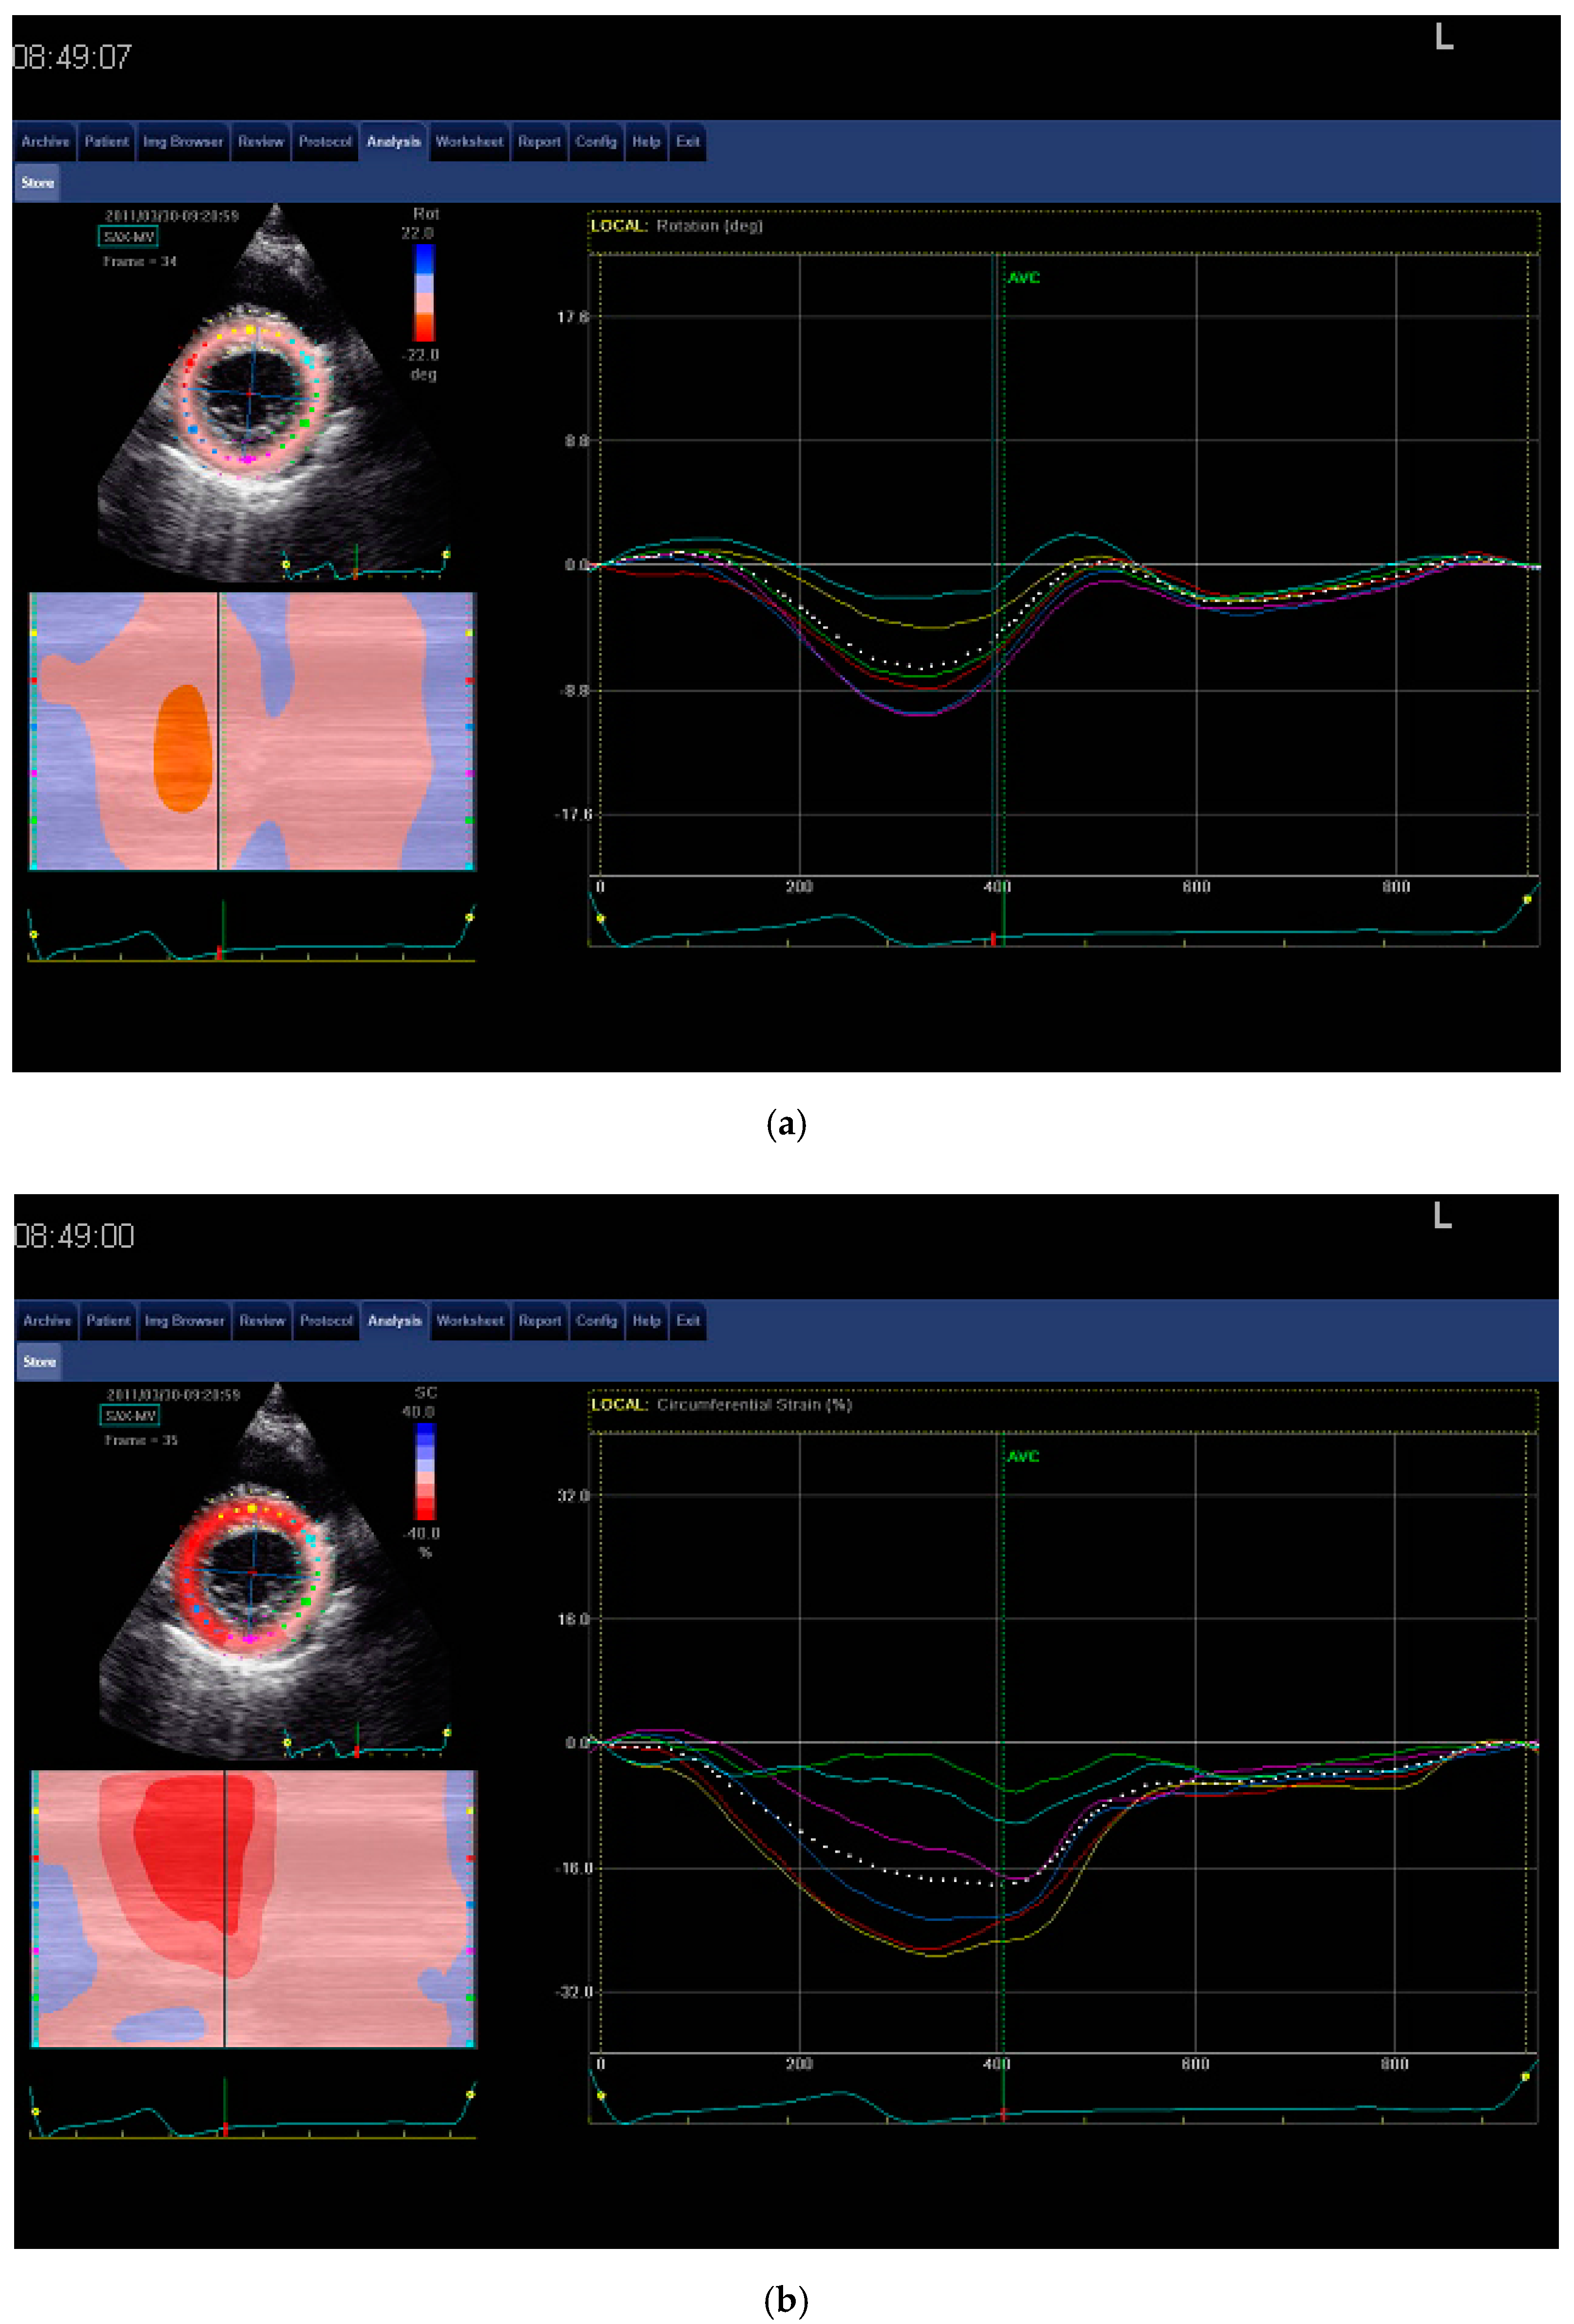

2.2.2. Speckle Tracking Echocardiography

Observer Variability